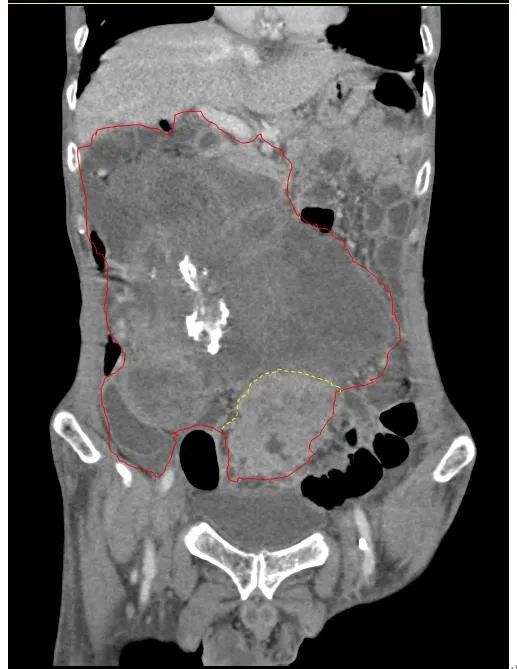

患者王大爺,男,72歲,發(fā)現(xiàn)腹腔腫物10余年,近兩年來患者雙下肢乏力、貧血,依靠間斷輸血維持著正常生活,出現(xiàn)頭昏,行動(dòng)困難,腹部疼痛及便血慕名來我院就診。入院后查體評(píng)估患者年齡大,體質(zhì)差,嚴(yán)重貧血,肺部感染及腸梗阻征象,腹部增強(qiáng)CT檢查提示腹膜后巨大腫瘤,長徑超過30厘米,占據(jù)大部分腹腔,并可能存在雙原發(fā)腫瘤。

苗滿園腫瘤外科團(tuán)隊(duì)在麻醉科/手術(shù)室的緊密配合下為該患者進(jìn)行手術(shù),術(shù)中發(fā)現(xiàn)腫瘤巨大,幾乎占據(jù)了整個(gè)腹腔,從左側(cè)向右腹腔延伸,向上將肝、腎擠向膈下,向左將胃及小腸擠向左上腹,向下深達(dá)盆腔內(nèi),包繞下腔靜脈、腸系膜上動(dòng)脈等大血管及輸尿管,回盲部及回腸也受侵犯。手術(shù)難度巨大,風(fēng)險(xiǎn)極高。團(tuán)隊(duì)?wèi){借著高超的手術(shù)技能和精準(zhǔn)的手術(shù)預(yù)案沉著應(yīng)對(duì),迎難而上,應(yīng)用高頻電刀、超聲刀、切割縫合器等先進(jìn)設(shè)備,耗時(shí)近5小時(shí)為患者切除了巨大腹腔腫瘤,并聯(lián)合右半結(jié)腸切除,術(shù)中出血僅50ml。術(shù)后病理為腹膜后巨大平滑肌瘤+回腸腺癌。